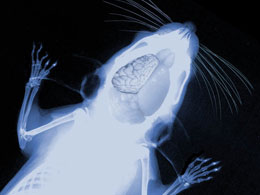

据ScienceNOW报道,一项近期刊登在在《细胞》(Cell)上的研究称,科学家发现了一种基因突变会导致哺乳动物神经组织扩大折叠。当他们变异实验鼠的这种基因,老鼠的大脑看起来更像人类了。

为了检验这一假说,他们利用RNA干扰技术修改了小鼠胚胎大脑中的TRNP1基因表达,发现小鼠大脑发育出了皮质折叠。